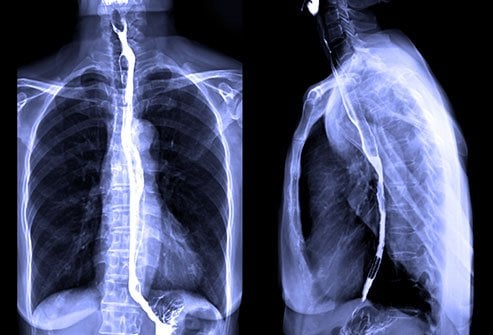

Barium Swallow

عکس رنگی از مری و معده رادیولوژیست قادر خواهد بود تصاویری از دستگاه گوارش؛ پشت دهان ، گلو (حلق) ، و مری داشته باشد. باریم ،فقط برای آزمایشهای تصویر برداری دستگاه گوارش انجام میشود.